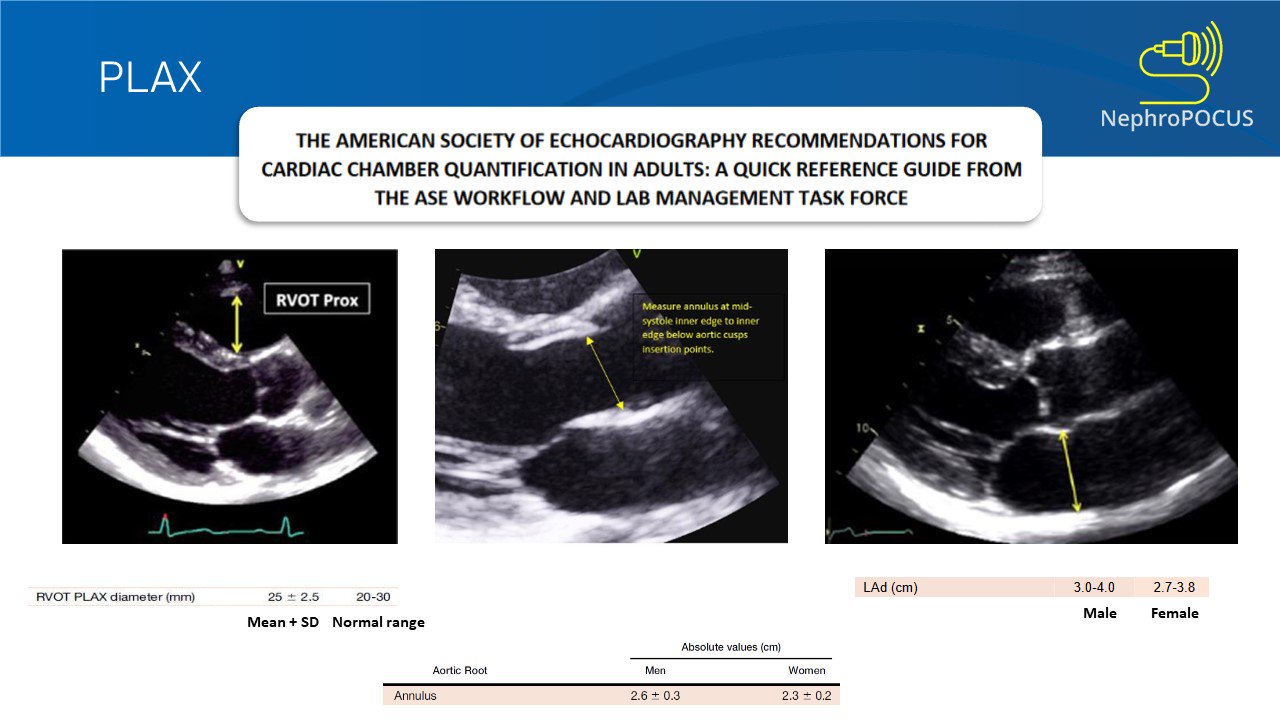

More great stuff from the Nephropocus legends!